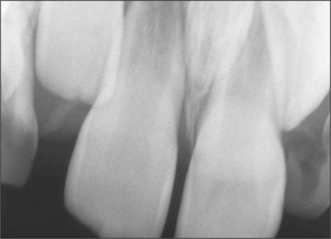

root morphology (Fig. 5.5)—number, length, shape; fused or separate, apex curved or bulbous; loss of periodontal width—ankylosis?

image

Fig. 5.5 Marked curvature of the roots of the lower third molars. Note gross caries affecting the lower left third molar.